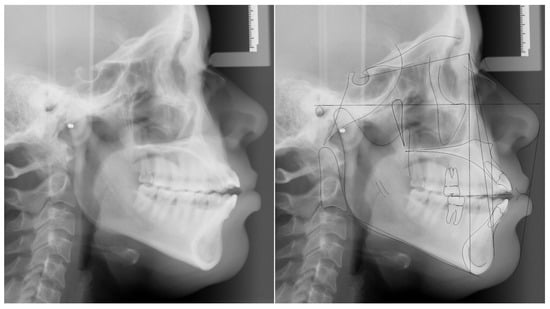

2. Case Presentation

2.1. Diagnosis and Etiology

| Measurement | A (Initial) | B (Final) | Difference (A-B) |

|---|---|---|---|

| SNA° | 89.6 | 89.3 | 0.3 |

| SNB° | 84.7 | 84.6 | 0.1 |

| ANB° | 4.9 | 4.7 | 0.2 |

| SN-MP° | 38.7 | 37.5 | 1.2 |

| FMA° | 26.3 | 25.3 | 1.0 |

| UI TO NA mm | 6.8 | 5.7 | 1.1 |

| UI TO SN° | 119.6 | 115.1 | 4.5 |

| LI TO NB mm | 11.0 | 10.5 | 0.5 |

| LI TO MP° | 97.8 | 96.0 | 1.8 |

| U Lip to E-Line | −1.3 | −1.3 | 0.0 |

| L Lip to E-Line | 2.7 | 2.5 | 0.2 |